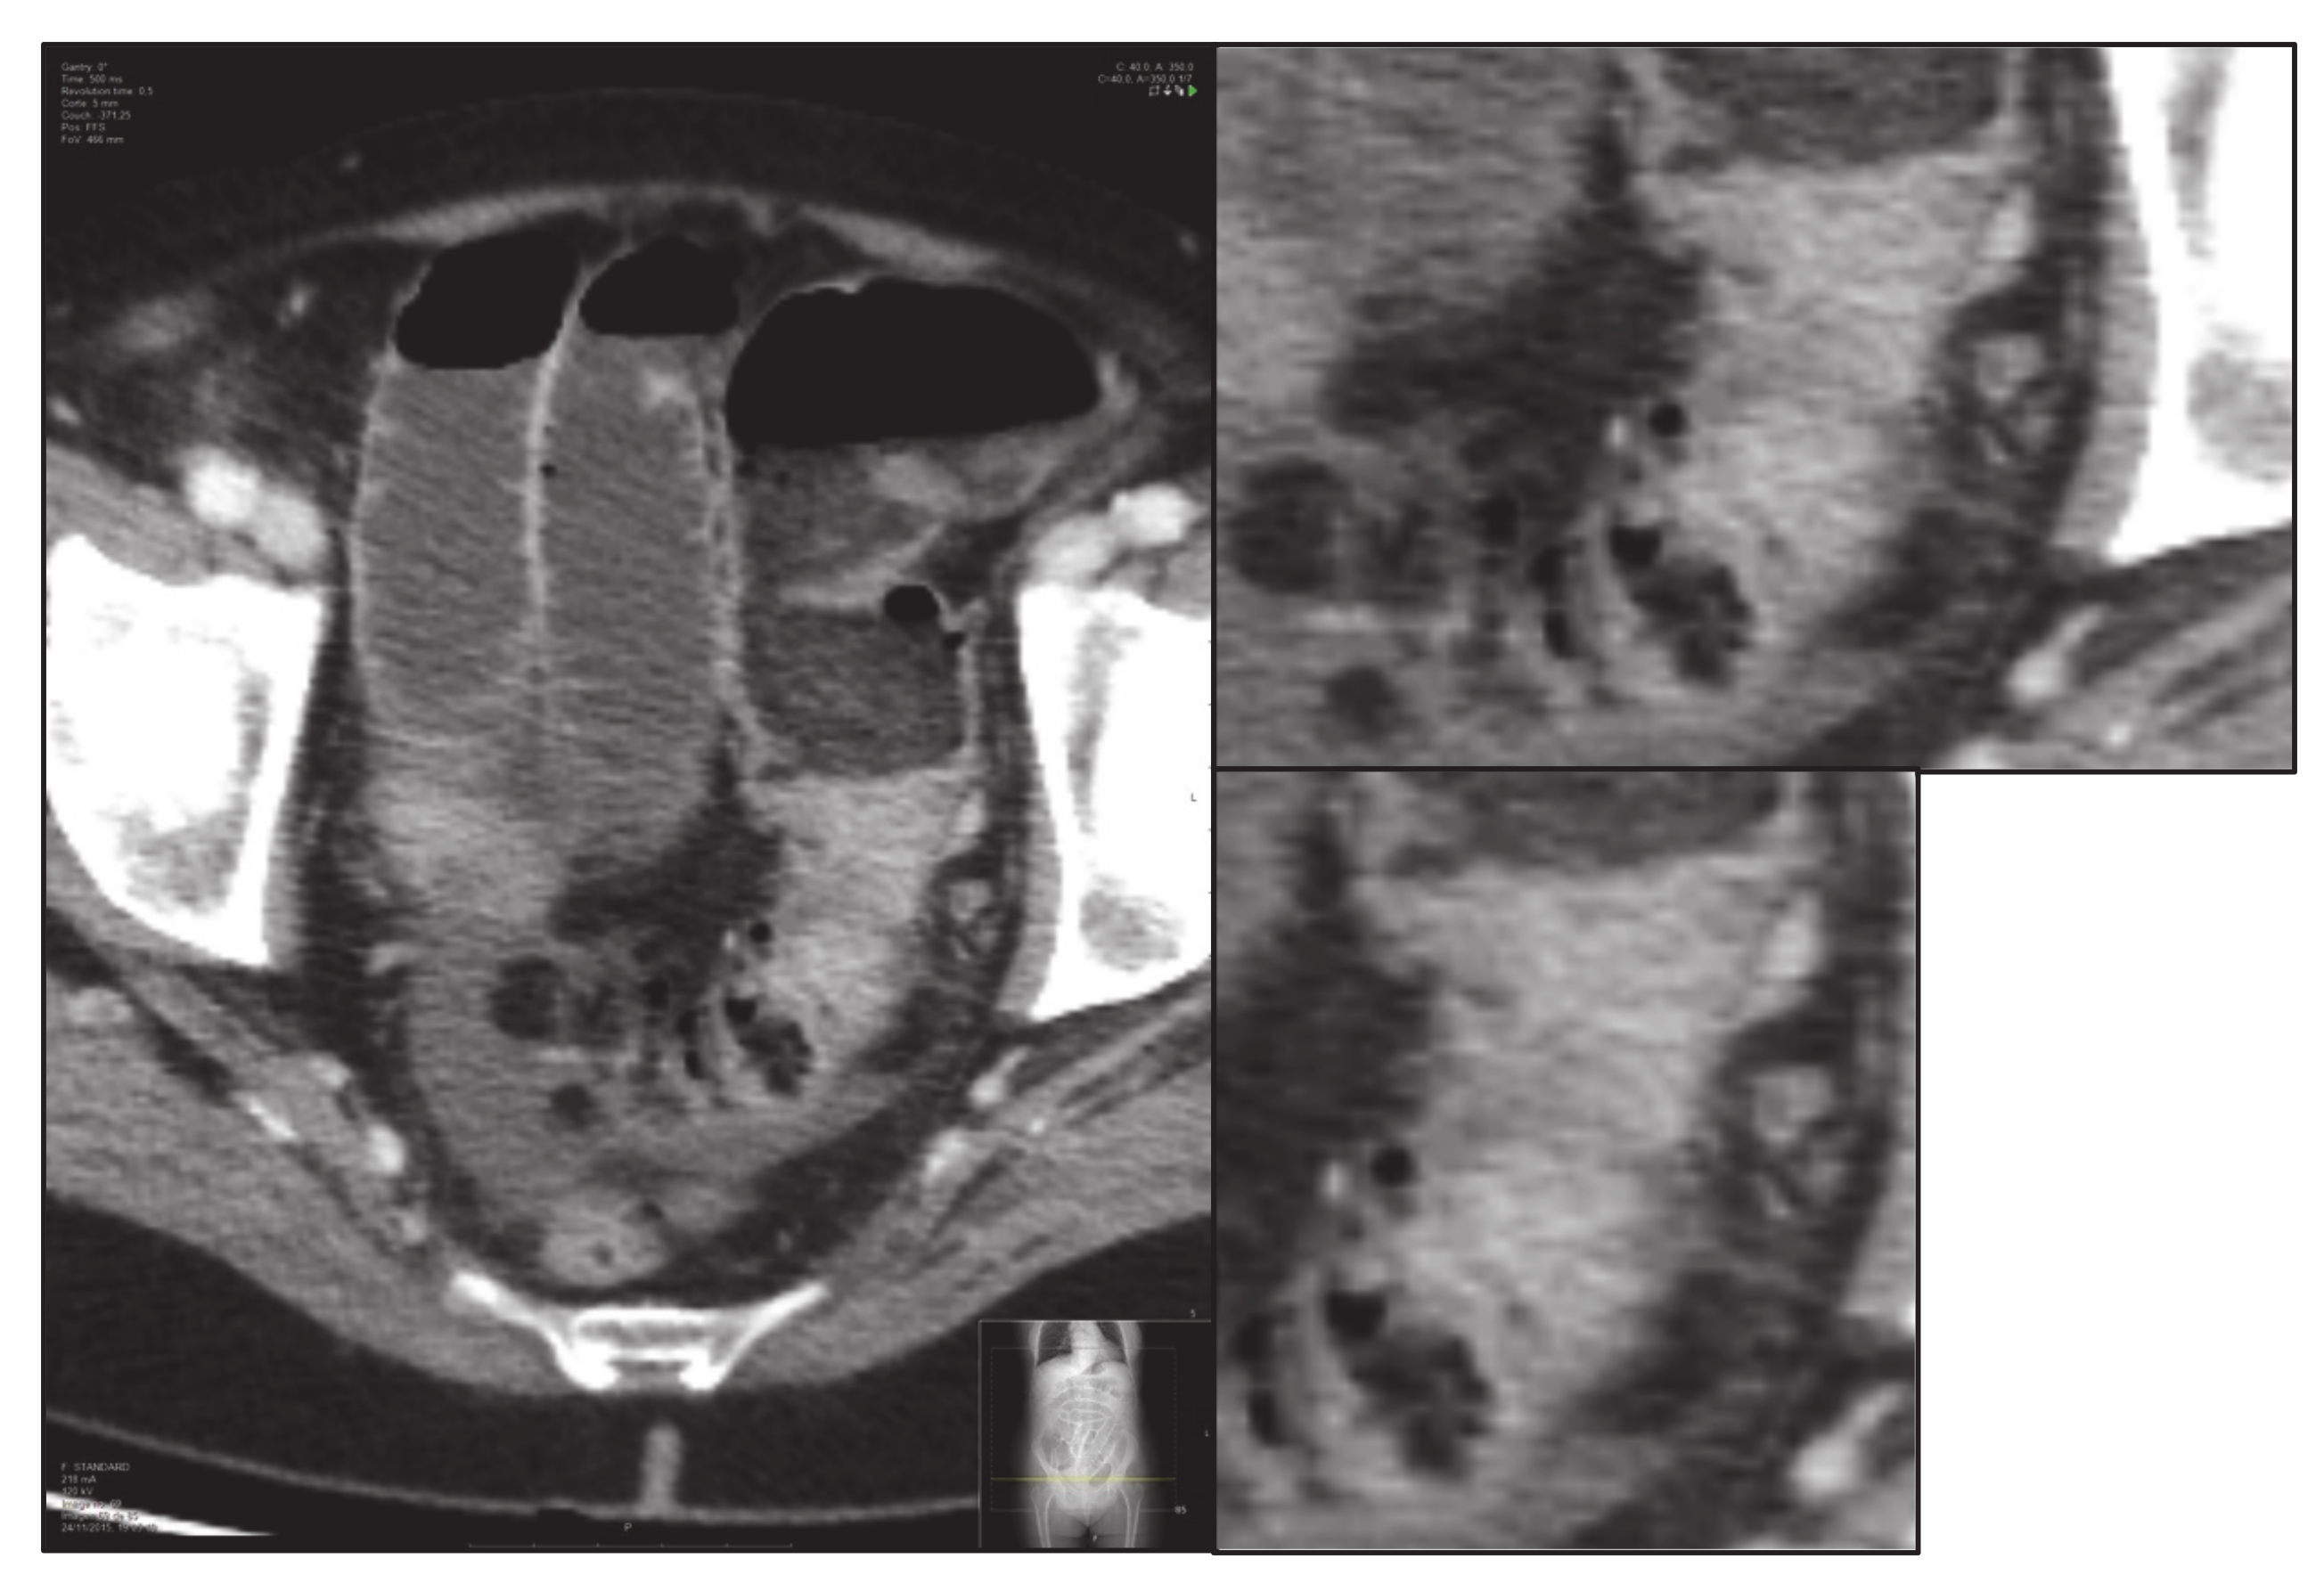

- Finally, without modifying the zoom, the previous delimitation is eliminated, and one image of the tumour is saved without delimiting and enlarged: “small-original.tiff” (i.e., Figure 4).